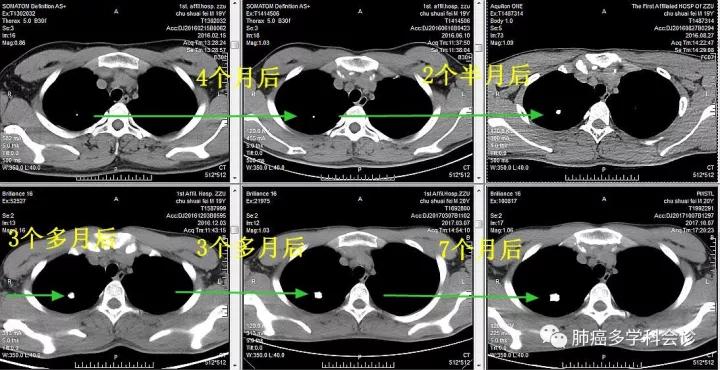

2016-2-15,胸部 CT 首次发现右肺上叶小钙化灶,较 2015-1-12 为新发。

2016年6月、8月、12月和2017年3月均在CT片上发现此钙化灶,渐增大,但没有引起医生们重视。

2017年10月复查CT(距上次检查 7 个月),钙化灶进一步增大,考虑骨肉瘤转移,全身骨骼ECT 扫描除显示右股骨术后改变外,未发现异常。胸外科医生切除了肺内钙化灶,病理报骨肉瘤肺转移。

2.  此例患者肺内钙化灶生长相对缓慢,短期内变化不著,如果把历次的CT图像放在一起比较就容易发现其变化。